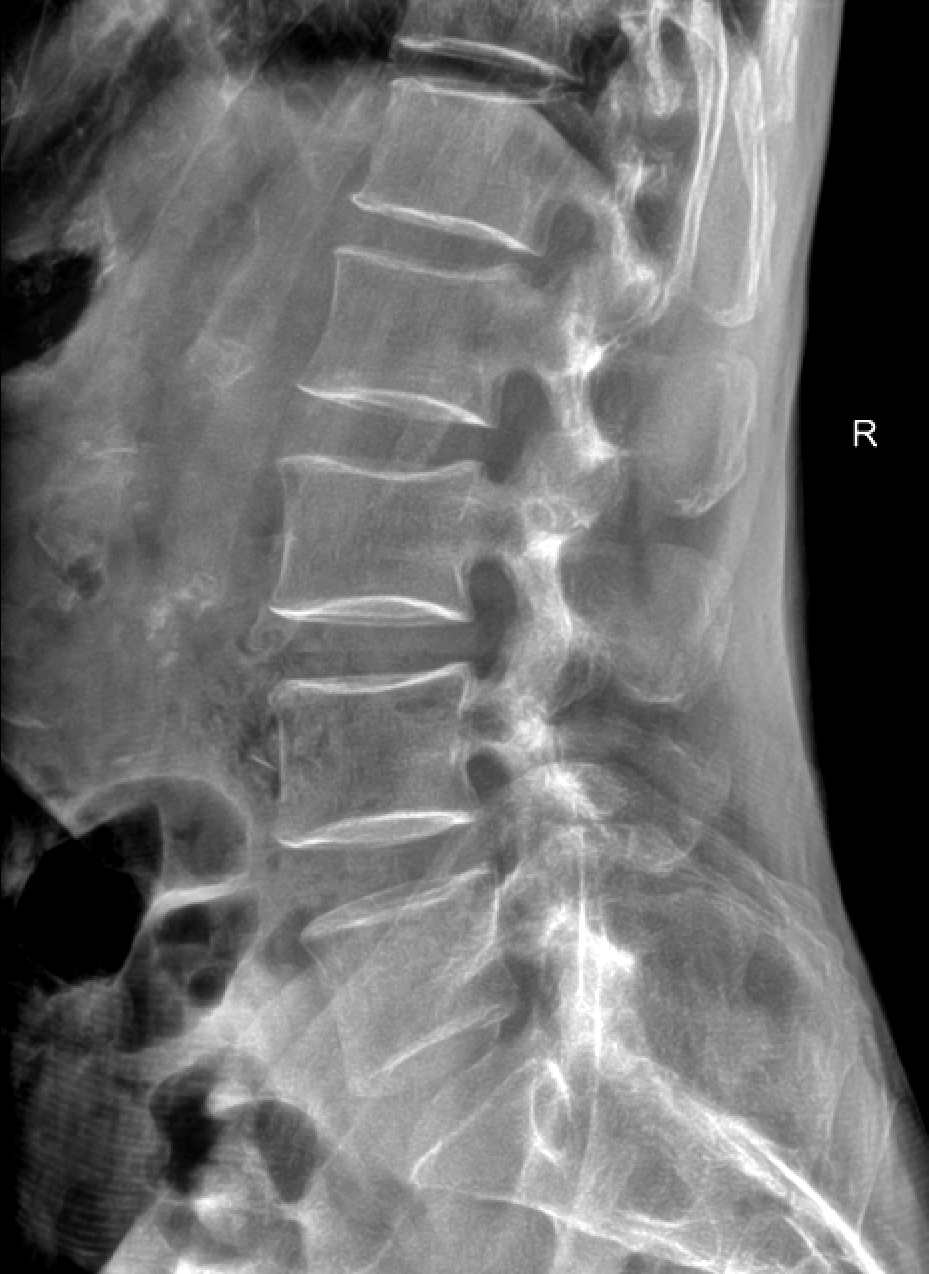

CT检查成像原理与DR类似,使用的是X射线,之后通过计算机成像。相较DR,CT可以多角度、多层面、多功能扫描成像,就像把一个面包切成多个平面进行观察。

检查应用范围:从头到脚,均可进行CT平扫,主要运用于头颅、颈部、胸部、腹部、脊柱、盆腔、四肢等部位。特别是高分辨率胸部CT,在检查肺部小结节时,运用非常广泛,CT检查脑出血也有相当的优势,另外微小的骨折、大部分器官的病变都能够看到。

而CT检查是把面包切片来看,获得的是真正的断面图像,没有层面以外的结构干扰。虽然细节看的更清楚了,但它就不是一块完整的面包了。

DR和CT是两种不同的检查方法,其侧重点不同,各具优势,两者不能互相替代。比如对于骨折来说,DR诊断要比CT更好,因为DR可以直接排除绝大多数的骨折,但是对于隐形性的骨折,CT会更好一些,可以作为DR检查后的进一步定性检查方法。